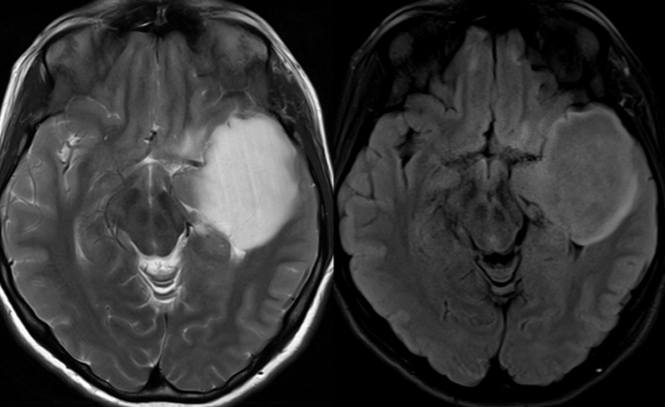

肿瘤显示 T2-FLAIR 错配征,尽管存在个小结节增强,但术后病理证实为 IDH 突变的胶质母细胞瘤

参数差异可能影响 T2-FLAIR 的呈现